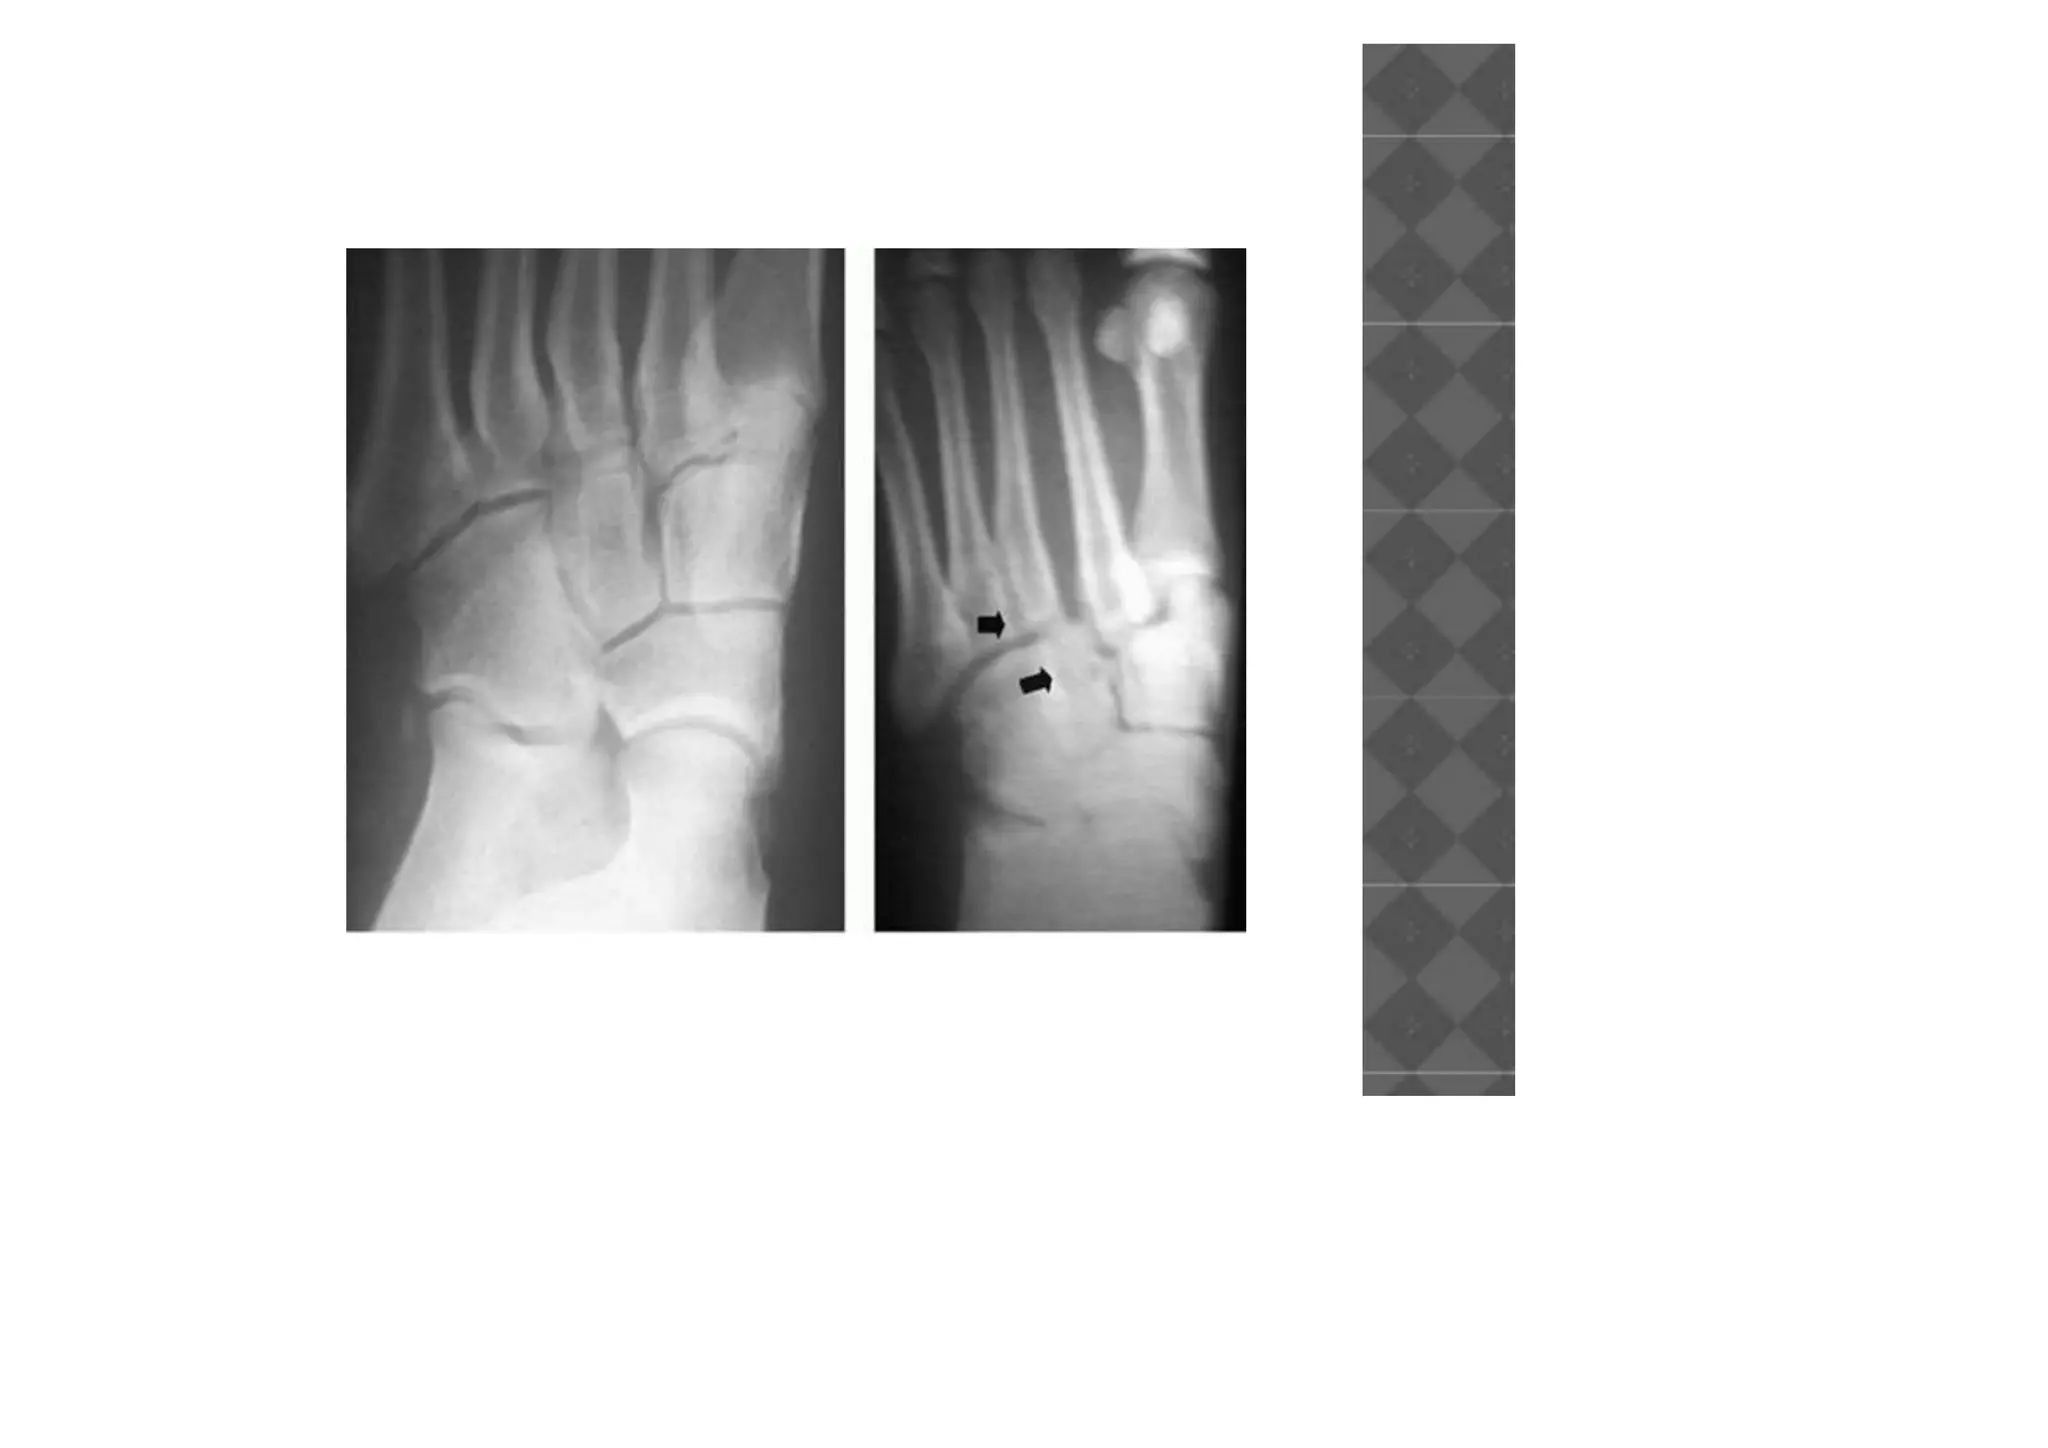

• Fleck fractures around the base of the

second metatarsal are indicative of

disruption of Lisfranc joint.

• Weight-bearing radiographs provide a stress

film of the joint complex.

• Stress views can be obtained.

• CT scan to assess intraarticular comminution.

• Dorsal displacementof the metatarsals on the lateral view is indicative of ligamentous compromise. • Fleck fractures around the base of the second metatarsal are indicative of disruption of Lisfranc joint.

• Weight-bearing radiographsprovide a stress film of the joint complex. • Stress views can be obtained. • CT scan to assess intraarticular comminution.

• #33 ). ■ Remove any debris from the Lisfranc region between the base of the second metatarsal and the medial cuneiform to allow the space to be reduced. Reduce thefirst tarsometatarsal joint and hold it with guidewires for cannulated screws. Place a screw from the dorsal aspect of the first metatarsal into the medial cuneiform

• #34 ■ Under fluoroscopic guidance, pass a guidewire from the medial cuneiform into the base of the second metatarsal while holding the reduction with a towel clip. Place the appropriate 4.0-mm cannulated screw over the guidewire